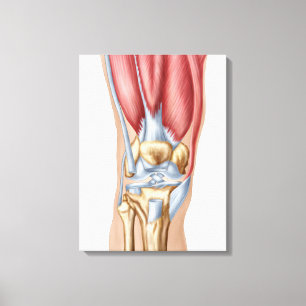

Lienzo Ilustracion médico del sistema muscular masculino

Precio 187,00 €